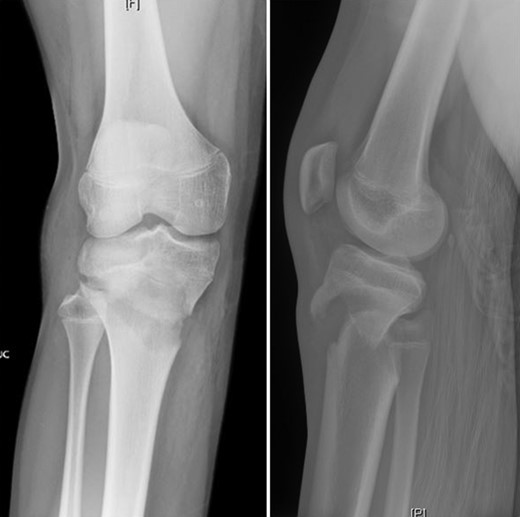

Patient is a 14-year-old male who slipped and fell while jumping off of a diving board and landed onto a flexed right knee. The patient was stable on presentation and neurovascularly intact with the knee locked in flexion. Skin was tenting anteriorly over the tibial tubercle and his compartments were swollen but compressible. A single plain film view (Fig. 1) was obtained prior to orthopaedic consultation. Closed reduction under sedation and splitting was attempted in the ED with partial but unsatisfactory improvement. Post-reduction radiographs (Fig. 2) demonstrated a tibial tubercle fracture with extension through the entire proximal tibial physis with metaphyseal involvement posteromedially. We classified this as a type IV tibial tubercle fracture, Salter–Harris II variant. In conjunction with patient and family we planned for urgent closed versus open reduction and application of knee-spanning external fixator. Immediately prior to surgery in the pre-operative holding area, the patient noted increasing right leg pain. In the operating room (OR), a marked increase in swelling with tense skin was observed. Due to rapidly progressive swelling and nature of the fracture, the decision was made to proceed with a 4-compartment fasciotomy of the right leg. The medial-sided fasciotomy (Fig. 3) revealed significant bulging of the superficial and deep compartments; however, the anterior and lateral compartments were less swollen. The fracture was unable to be closed reduced intraoperatively, therefore proximal extension of the medial fasciotomy wound was performed to open and reduce the fracture under direct visualization. Anatomic reduction was achieved and a knee-spanning external fixator was applied (Fig. 4). Approximately 72 hours later the patient was brought back to the OR for irrigation and debridement, lateral wound closure, and medial wound vacuum placement. Another 72 hours later, he returned to the OR for removal of the external fixator, ORIF, and split-thickness skin grafting of the medial fasciotomy site. An anterolateral approach was used with a 3.5 mm proximal tibial locking plate (Fig. 5). At most recent follow-up (Fig. 6), six months post-op, the patient is pain free, ambulating without assistive device, and has returned to all desired activities.

Presenting plain film view demonstrating proximal tibia fracture.